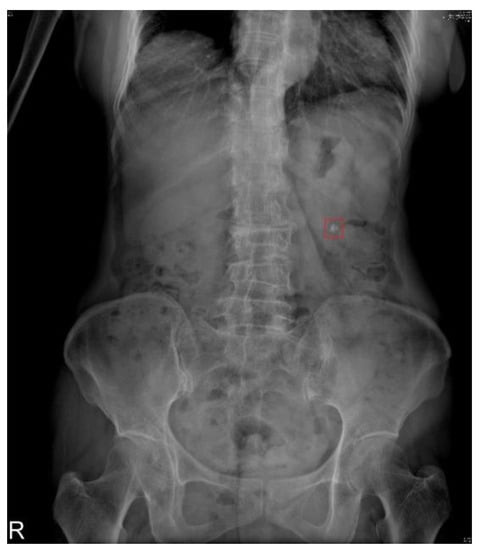

2.2. Datasets

2.3. Image Preprocessing

3.4. Subsystem 2—Segmentation Model for Medical Images